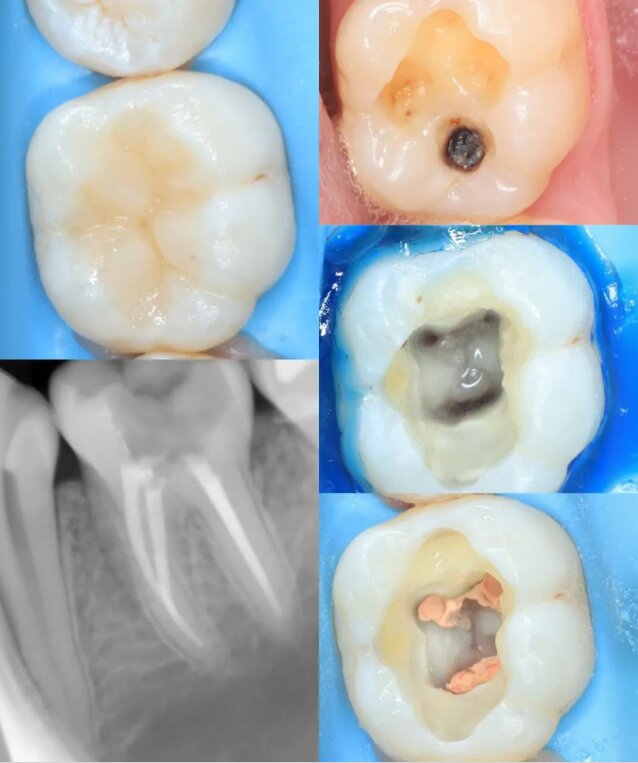

Портфоліо лікаря

У портфоліо представлені реальні клінічні випадки з практики лікаря — від первинного стану до результату лікування. Кожен кейс демонструє індивідуальний підхід, сучасні методи лікування та увагу до деталей